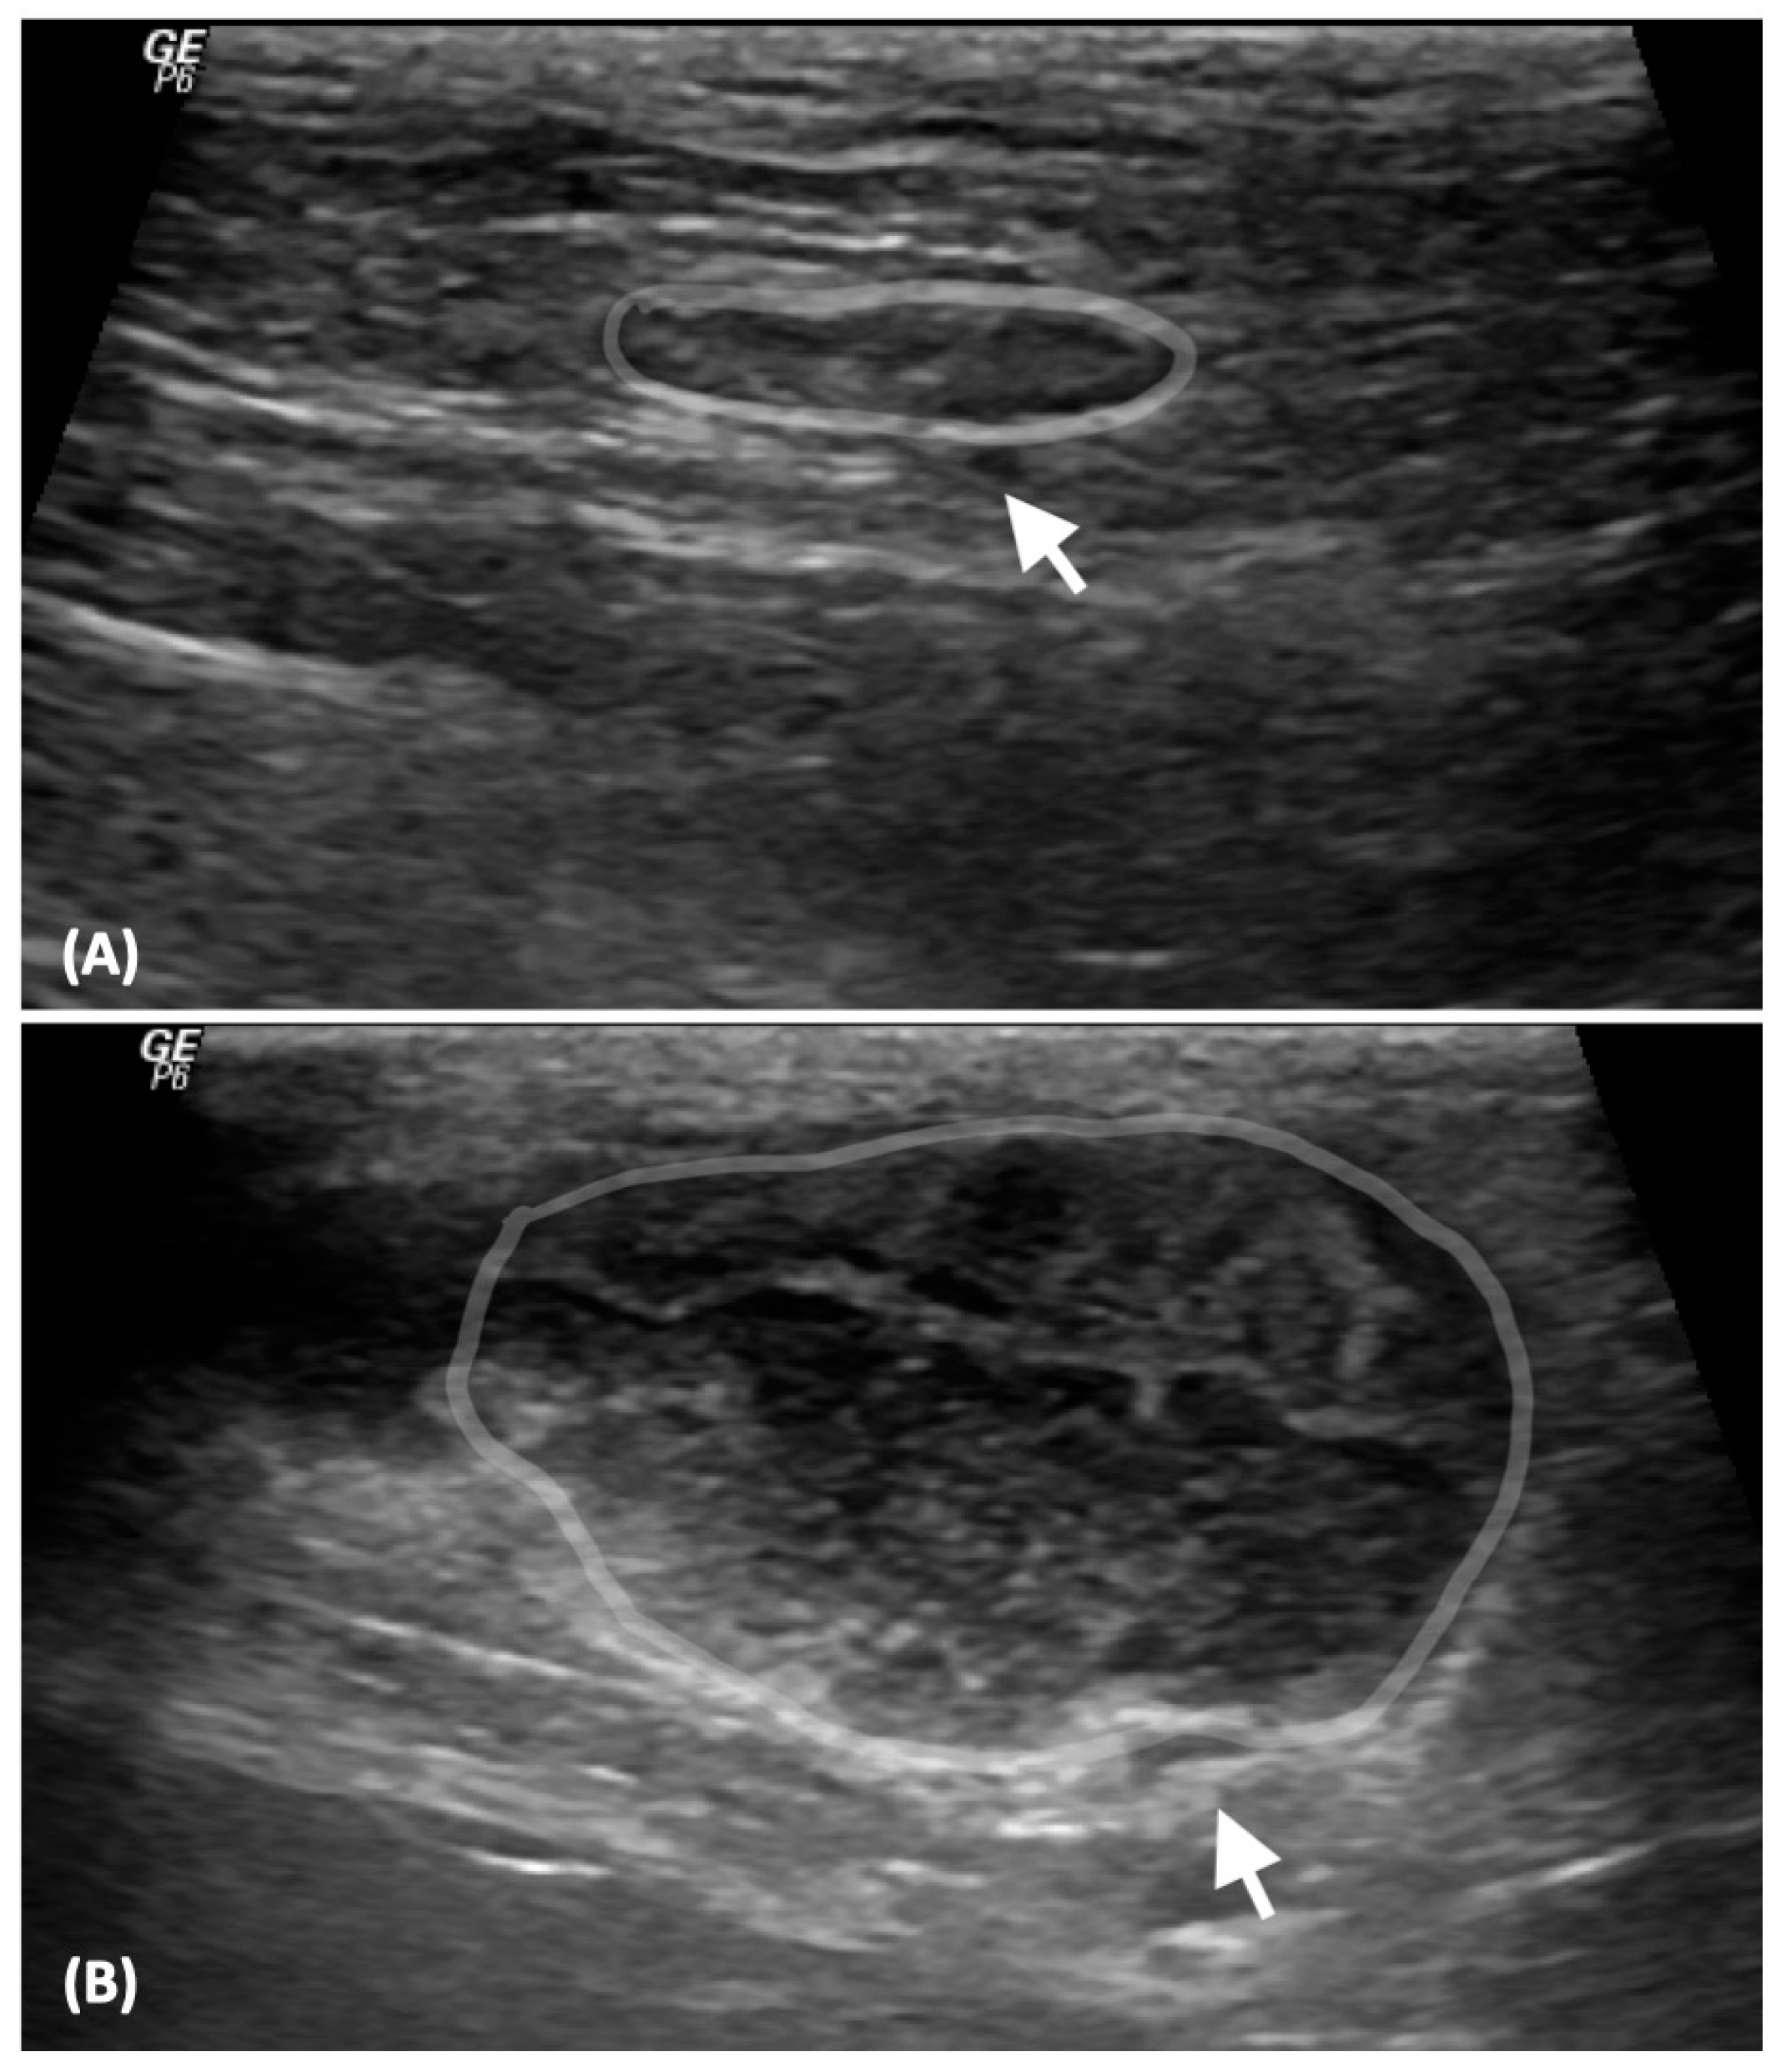

2.2. Analysis of Ultrasonographic Images